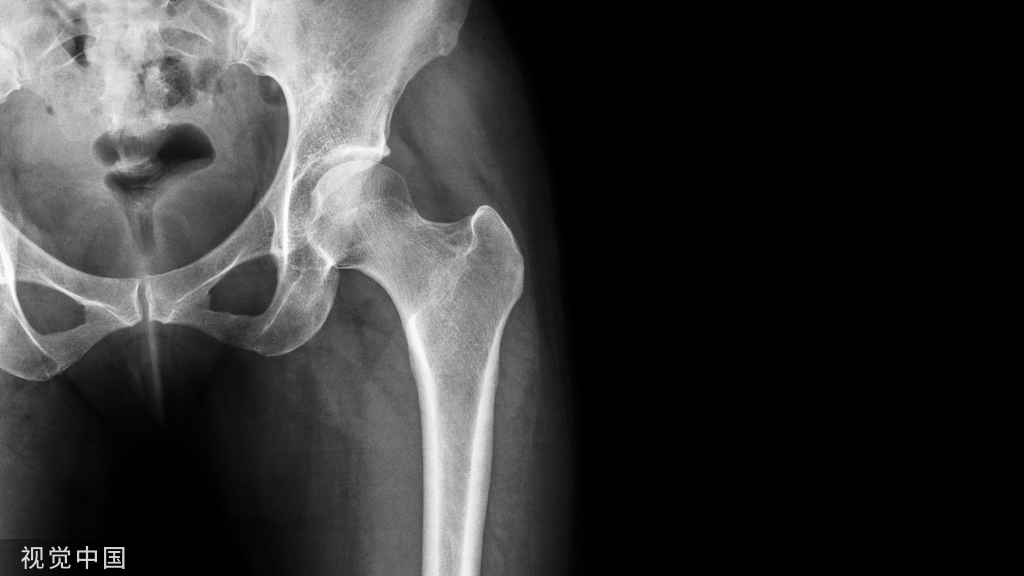

髋关节

- CE角(Wiberg 的中心边缘角):即两侧股骨头中心连线的垂线和髋臼外缘股骨头中心连线所成的夹角。

- 正常值:20°~35°

- 临床意义:主要用于评估髋臼的包容性,髋臼发育不良时夹角变小。

- Sharp角:即双侧泪滴下端连线与泪滴下端至髋臼上缘连线所成的角。

- 正常值:33°~38°

- 临床意义:<32°很少见且无临床意义39°~42°为正常值的上限,42°~47°需动态观察,>47°可认为异常。评价髋臼发育和髋臼对股骨头的覆盖情况。

- 髋臼指数(actebular index,AI,亦称髋臼角):髂骨最下缘与髋臼最外缘的连线与H线的夹角(H线,即Hilgenreiner线,组成两侧髋臼髂骨最下缘的连线),适合于“Y”型软骨尚未闭合的儿童(≤10岁)髋臼的测量。

- 正常值:国外一些学者也测量了1~2岁婴幼儿的正常值范围,认为1岁婴儿的正常值在25°~30°之间,2岁一般低于20°,而超过30°为异常。

- 临床意义:评价髋臼发育和髋臼对股骨头的覆盖情况。

- 髋臼杯外展角:即在骨盆正位片上髋臼杯上缘和下缘连线与水平线的夹角。

- 正常值:45°~55°

- 临床意义:外展角过大容易发生髋关节内收时撞击,假体外上缘应力集中和髋关节不稳,并向后上方脱位。髋臼杯外展角>55°时,其股骨头假体受力方向由内上逐渐变化指向外上 ,脱位机率明显增加。

D’Lima等研究认为45°~55°的外展角对髋关节的活动度和稳定性来说是最合适的,在此范围内髋臼杯对股骨头的覆盖较好,与股骨头表面接触较多,应力分布均匀,关节稳定。